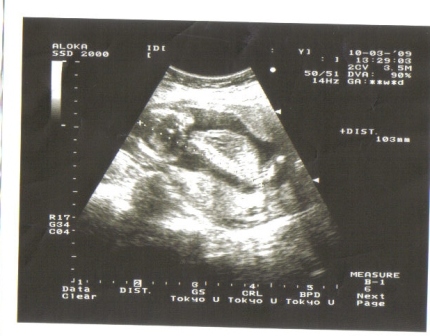

Rég voltam, így alig győzök visszaolvasni, hogy mennyi mindent írtatok. Kis gyorshír rólunk, mielőtt még mindent alaposan végigolvasok. Tegnap voltunk UH-n, elvileg ugye 19+4-nél, mert ahogyan Linacskánál, nálunk is a betöltött 19. hét után javasolták a genetikai szűrést. Szerencsére a gyerkőcnél minden rendben, most már 100%, hogy fiú, azzal viszont jól meglepett minket, hogy a biometriai adatai alapján 21+3-nál tartunk. :shock: Kérdeztem a szonográfust, hogy ez OK-e, azt mondta, hogy nem nagyon szokott ilyen lenni, mert a babák kb a 25. hétig majdnem ugyanakkorák, és csak utána kezdenek el különböző ütemben nőni. Azért remélem, hogy nem lesz a gyerkőc óriásbébi,úgy látszik, nagyon akar nőni. Mindenesetre minden rendben vele, szóval aggódni nem aggódom azért annyira :)